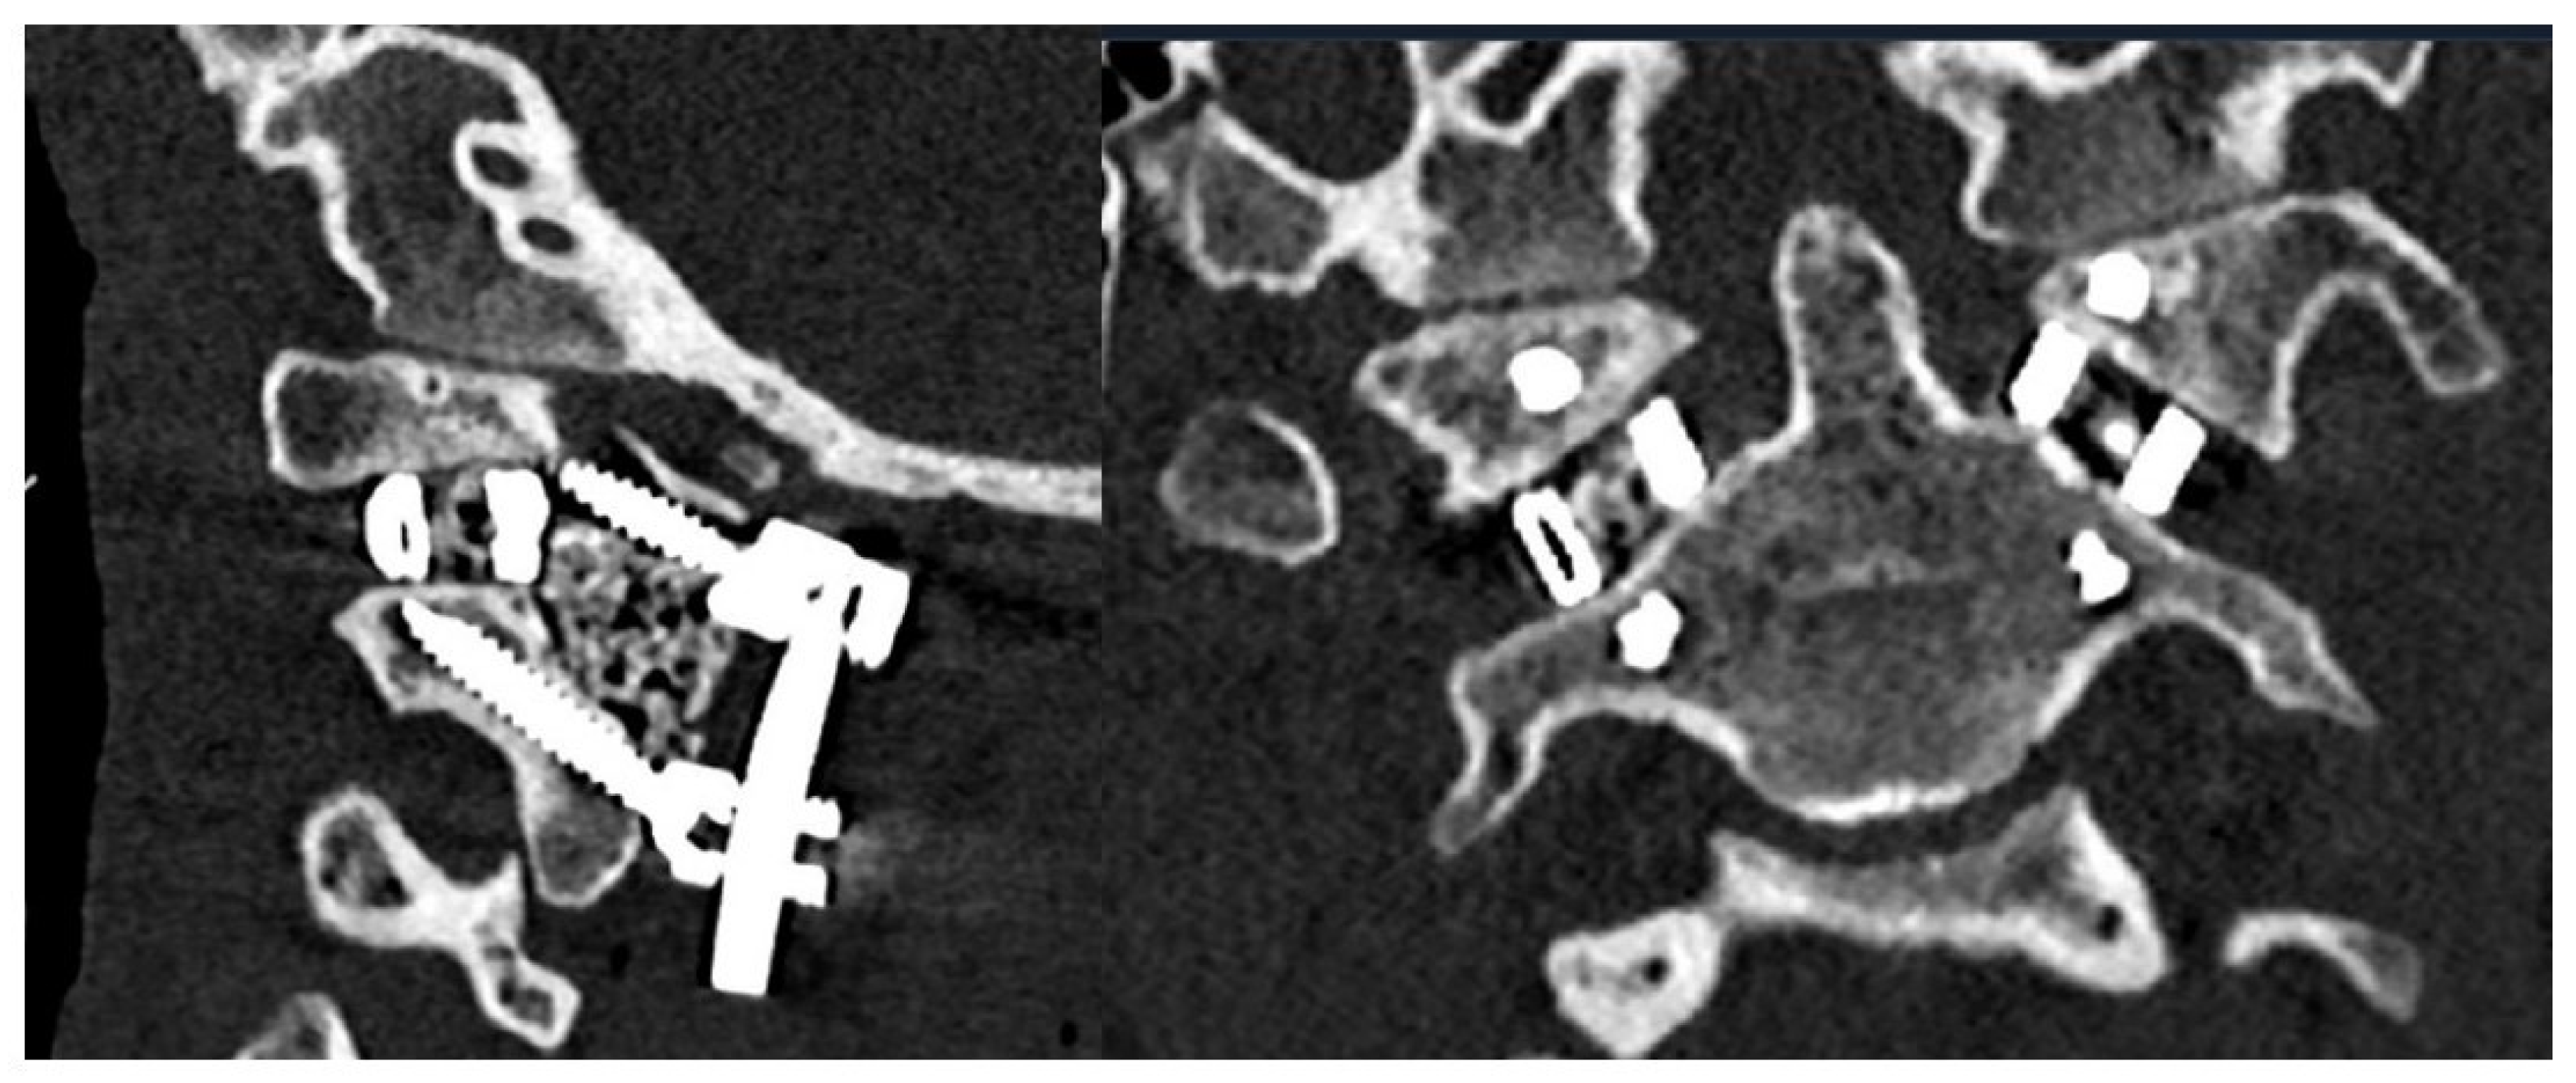

3.2. Surgical Approach

4. Results